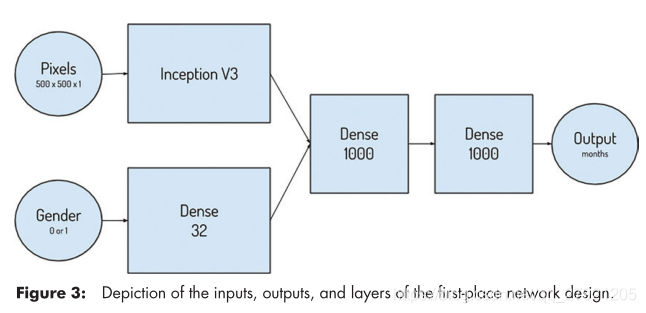

第一名:Alexander Bilbily等16 Bit公司-MAD=4.265

输入:500x500,基本网络inception V3,数据增强

特点:结合了性别信息

结果:多模型融合

网络: